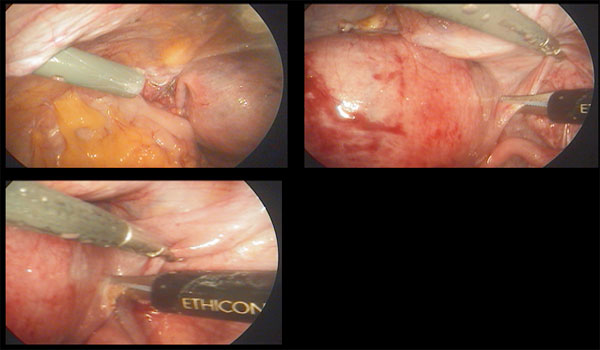

- மருந்துகள் மூலம் குணம் ஆகவில்லை என்றால் லேப்ராஸ்கோப்பி முறையில் அந்த நீர் கட்டிகளை உடைத்து விடவேண்டும்.

- அதற்கு கட்டியை மட்டும் எடுப்பதா-கர்ப்பபை முழுவதும் எடுப்பதா—ஓபன் அறுவைசிகிச்சையா-லேப்ராஸ்கோபியா என்பது நோயாளியின் வியாதியின் தன்மையை பொருத்து மாறும்